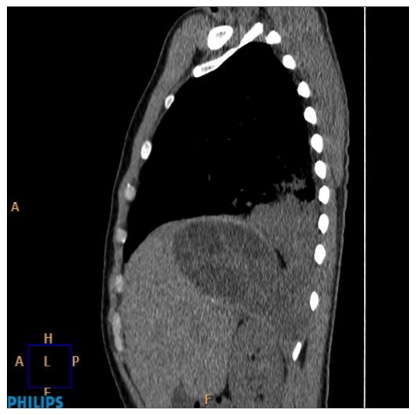

Se procede a realizar un TC abdominal:

Elevación del hemidiafragma derecho una lesión quistíca de gran tamaño en segmento VII que continua con el segmento VI. Que pierde plano de clivaje con espacio pararrenal anterior

Estamos presenciando el lugar de afectación más frecuente de la Hidatidosis, el Hígado, concretamente sería el lóbulo hepático derecho, el cual se ha abierto al hemitórax derecho por una rotura directa.

- TC: Tiene mayor S y E para la valoracion del quiste hidatídico. Se usa cuando la ecografía no nos proporciona un resultado óptimo por obesidad, interposición de gas, cambios postquirúrgicos en la pared abdominal, deformidades, etc… La administración de contraste no es necesaria a menos que se sospechen complicaciones, especialmente la infección o la comunicación con la vía biliar. Los hallazgos por TC son similares a los de ultrasonido, como son la densidad líquido en el interior del quiste, vesículas hijas en la perifería del quiste mayor o madre o calcificación de pared. La pared del quiste muestra alta atenuación inclusive sin contraste y sin calcificación.